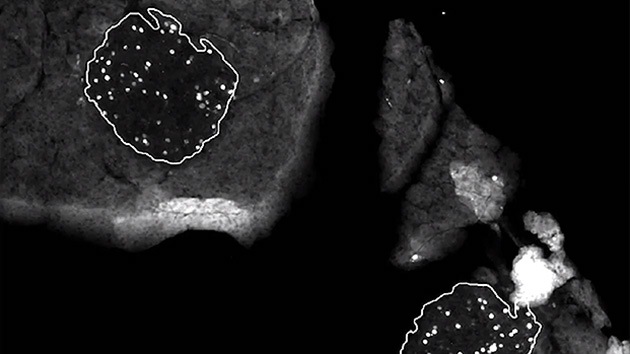

En ambas enfermedades, y por causas diferentes, el origen es el mismo: la destrucción de las células beta-pancreáticas encargadas de producir la insulina que el organismo necesita. Hasta ahora, todos los intentos por regenerar estas células han defraudado. Ni siquiera el propio Melton, codirector del Instituto de Células Madre de Harvard (en Boston, EEUU), ha logrado crear células madre capaces de regenerar a las productoras de insulina (y los trasplantes de islotes pancreáticos en los que se puso la esperanza hace unos años tampoco han funcionado).

La clave para descubrir la betatrofina la encontraron en el embarazo. Durante la gestación, el organismo multiplica de manera natural su producción de insulina para cubrir las necesidades del feto. Para ello, sus células beta-pancreáticas se expanden a un ritmo superior a lo normal y, como observaron en una rata preñada, probablemente lo hacen impulsadas por altos betatrofina.

Si durante el embarazo, las células beta-pancreáticas se replican a un ritmo cuatro veces superior a lo normal y hasta 4,5 con una inyección de glucosa; el tratamiento con betatrofina logró multiplicar esta producción de células fabricantes de insulina hasta 30 veces más de lo normal. Un dato que convertiría a la betatrofina -de confirmarse estos hallazgos en humanos- en un potente y eficaz sustituto de la insulina en el futuro.